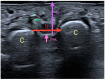

Results: The presence of MN and the factors associated with it were studied in 100 patients using ultrasound (US). The assessment and comparison with US of the space inferior to the DTML between M3 and M4 in control groups and patients with MN show that patients with MN have a smaller size in the variable "h" (height or distance DTML-plantar skin), in the variable "b" (base or intermetatarsal distance M3 and M4) and in the variable "s" (surface of the parallelogram "h" × "b"). The predictors of MN are a decrease in dimension "b" and an increase in weight. Sitting in an office chair and the use of a bicycle, due to equinus, have an influence on the space below the DTML, reducing it and promoting the appearance of MN.

Conclusions: The two US measurements ("h" and "b") in the space below the DTML are smaller in patients with MN than in the asymptomatic group. A shorter distance between M3 and M4, and an increase in BMI are predictors of MN.